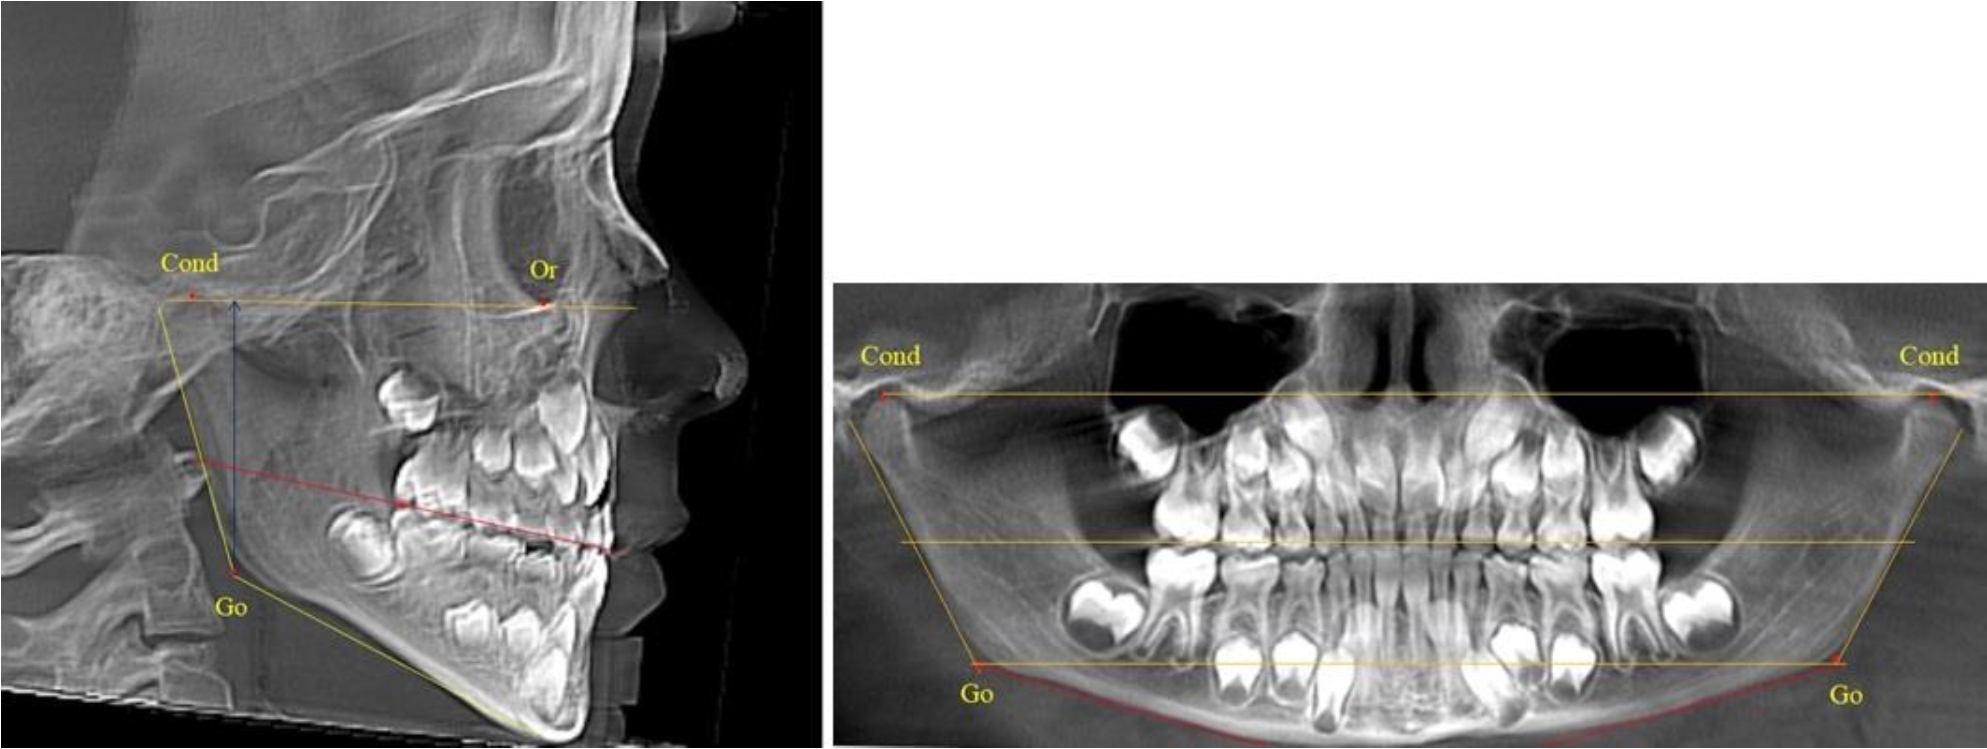

В 1-й группе были проанализированы 7 телерентгенограмм и 7 ортопантомограмм, что составило (6,60 ± 2,41) % от числа изученных рентгенограмм. На всех парах рентгенограмм угол нижней челюсти, измеренный на телерентгенограмме, соответствовал углу, полученному при построении угла на ортопантомограмме. Окклюзионная линия практически однотипно делила ветвь на два отдела (рис. 1).

Как на ортопантомограмме, так и на телерентгенограмме высота ветви у детей в периоде сформированного прикуса молочных зубов составляла (42,21 ± 2,48) мм. При этом высота верхней окклюзионно-суставной части была (22,57 ± 1,46) мм, а нижней – (19,64 ± 1,54) мм.

Учитывая вариабельность абсолютных величин, определи относительные показатели соразмерности частей ветви нижней челюсти. Так, отношение высоты верхней части ветви к нижней в среднем составляло 1,15 ± 0,13. Отношение общей высоты ветви к верхней ее части составляло 1,87 ± 0,14, а отношение общей высоты ветви к нижней ее части было 2,14 ± 0,16 и достоверных различий по относительному показателю отношения всей высоты к верхней и нижней челюсти нами не отмечено (р ˃ 0,05). При этом визуально обе части выглядели примерно равноразмерными.

Рис. 1. ТРГ и ОПТГ пациента 1-й группы